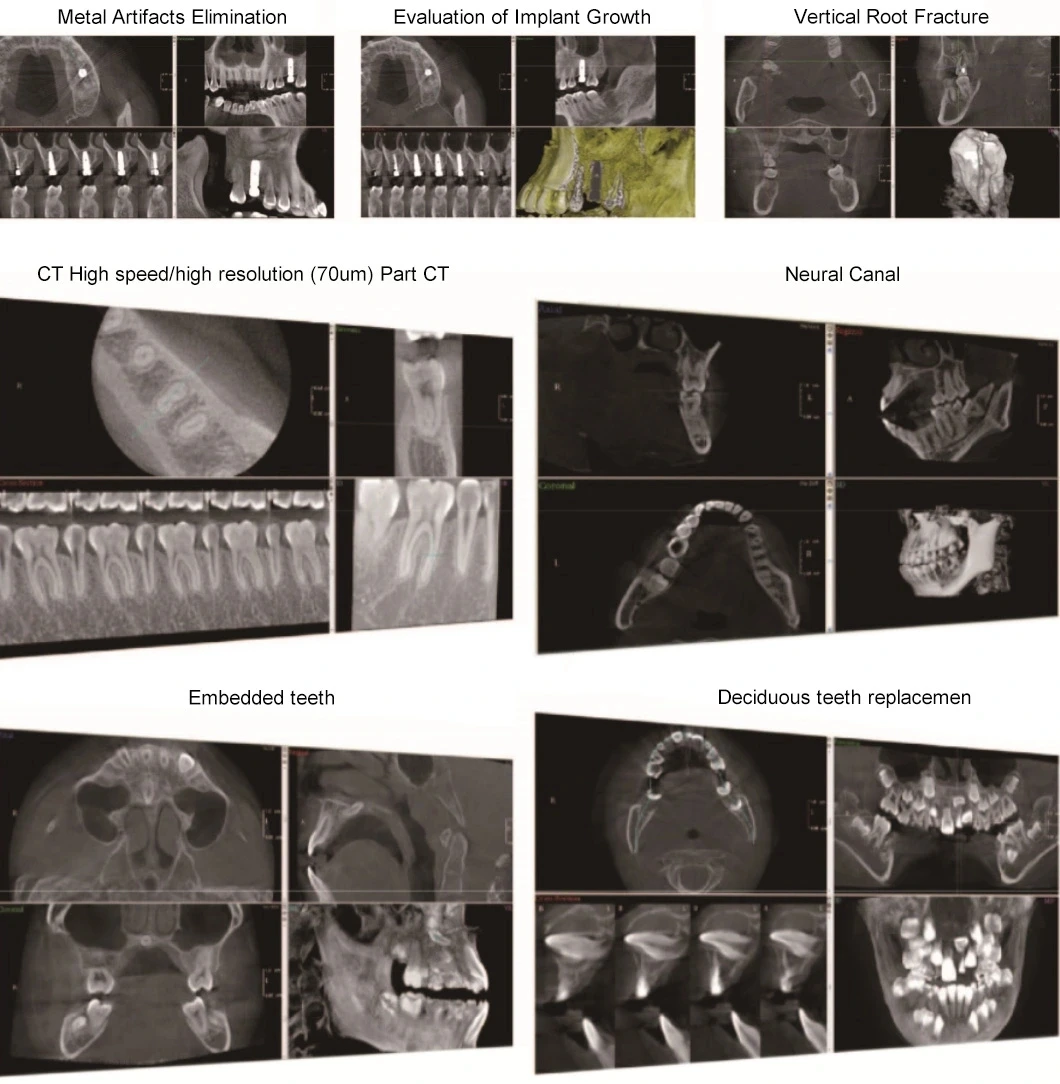

Presently cone beam CT is the most promising and revolutionary device of oral and skull imaging equipment. Its X-ray generator will move around the object for annular DR with low radiation, and after radiograph around the object for times (180°-360°), the jointed data will be reconstructed by the computer to get the 3D image. The application of CBCT has epoch-making meaning to oral health.

Digitalization mouth unit adopts unique HRBPR image reconstruction and WE image processing algorithm, and based on the super speed image reconstruction of CUDA technology, the NL-means image smoothing algorithm, and metal artifacts reduction algorithm etc, it provides the users 3D oral images with high resolution and high precision. Meanwhile, the applied pulse source technology can reduce the radiation level for patient and extend the lifetime of X-Ray tube.

The processing speed problem is solved by adopting advanced CUDA computing technology and the tomographic images will be generated after 10s.

After identify the metal area and reconstruct the image for second time, the metal artifacts will be reduced effectively through second reconstruction overlying.

The similarity of adjacent pixels is considered during image smoothing, which preserves the image details effectively at the same time.